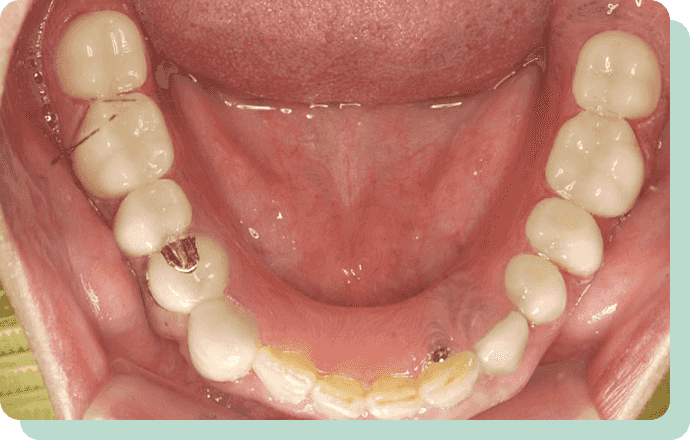

歯が少なくなり、どうしても入れ歯が安定しない場合は、インプラントを最小限適用して、安定させることも可能です。

写真の方の場合は、ホックのような材料を採用。

パチッと差し込む方法で装着するので、維持力が大きく増しました。

入れ歯を安定化させることで、しっかり噛めるというメリットもあります。

インプラント義歯

リスク:疼痛・咬合時痛・冷水痛・出血・歯ぐきへの損傷

費用:インプラント治療(1本あたり)250,000円

根面にキャップをかぶせて入れ歯に取り込んでいくことで、入れ歯の安定度を増すことが可能です。